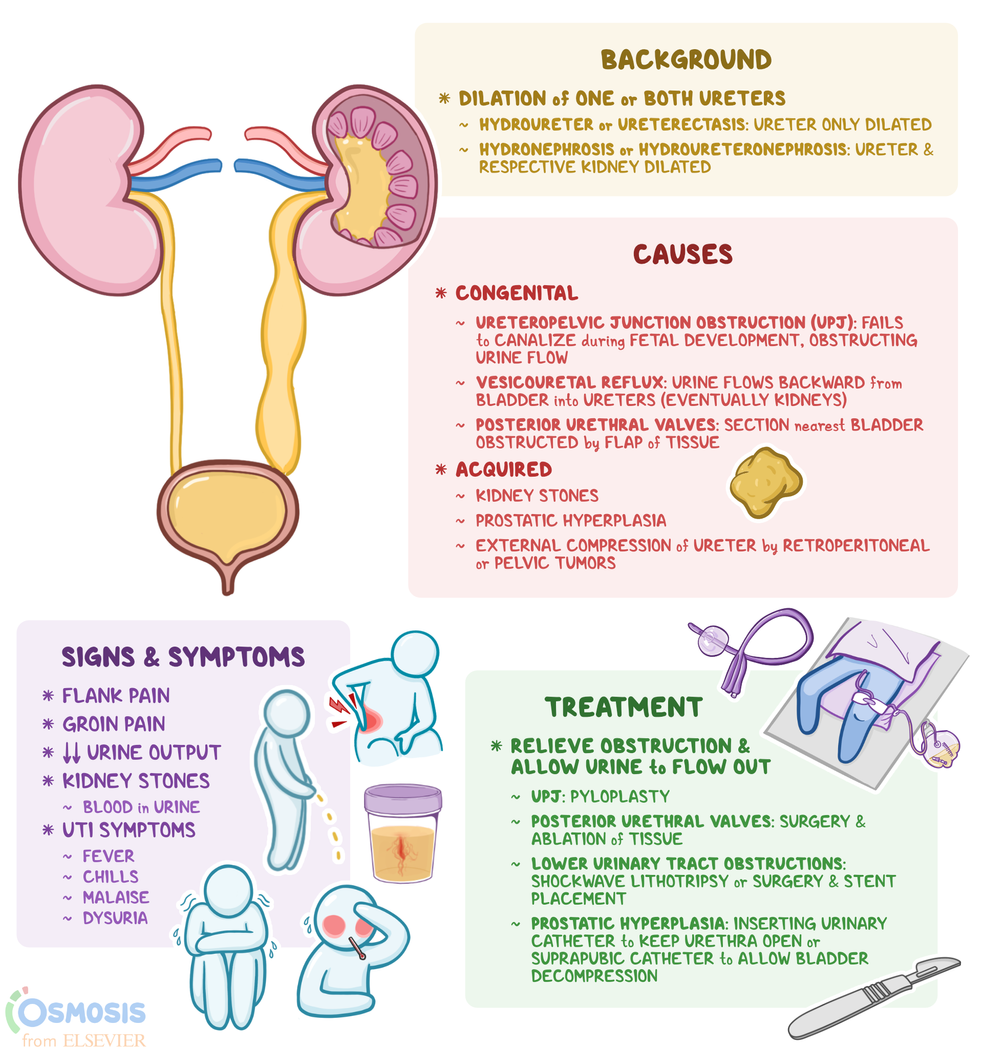

Ureterectasis What Is It Causes Treatment And More Osmosis